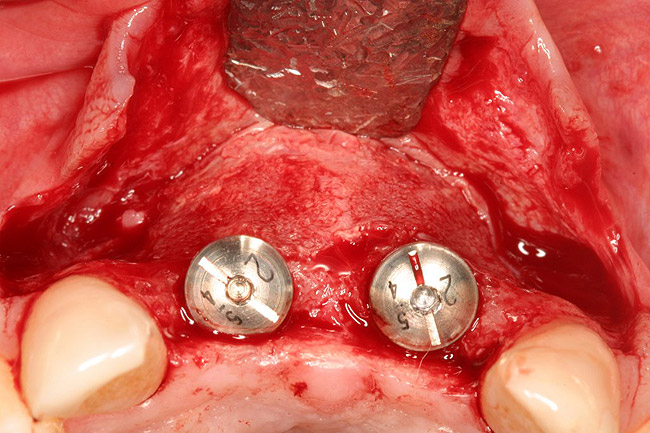

Figure 16   After extraction and 3 months of healing, two implants were placed in ideal position and with primary stability at sites Nos. 8 and 9. Implants were stable. Dehiscence defects exposing 13 threads were produced.

Figure 16